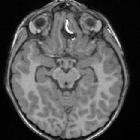

Duplication

of the pituitary gland. MRI Axial and Coronal T1 images showing complete duplication of the pituitary gland with two posterior bright spots